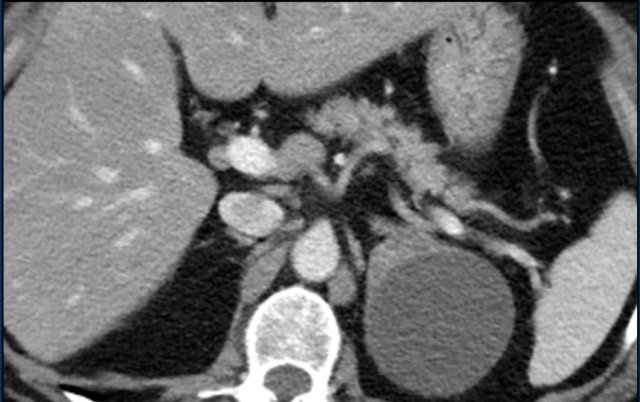

The images show bilateral adrenal incidentalomas found in a 64-year old patient scanned for analysis of an abdominal aneurysm.

The scan in the arterial phase shows bilateral lesions with a density of 50 HU.

On the non-enhanced CT performed a few days later, the density in both adrenal glands was less than 10 HU, proving these to be lipid-rich adenomas.